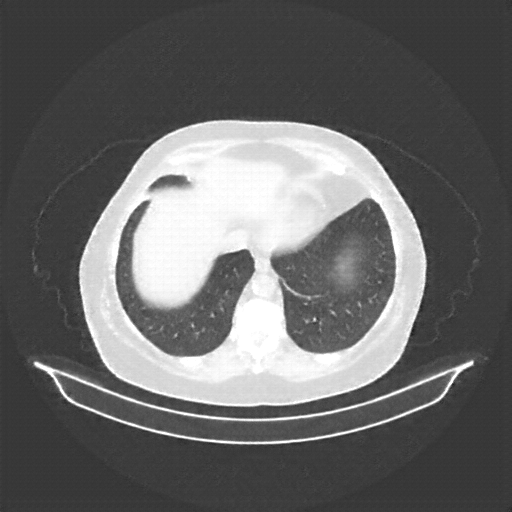

Reconstructed NATIVE CT scan (cycle consistency)

Full window (WL 1023.5, WW 4095 β†’ Low βˆ’1024, High +3071)

Lung window (WL -600, WW 1500 β†’ Low βˆ’1350, High +150)

Mediastinum window (WL 40, WW 400 β†’ Low βˆ’160, High +240)